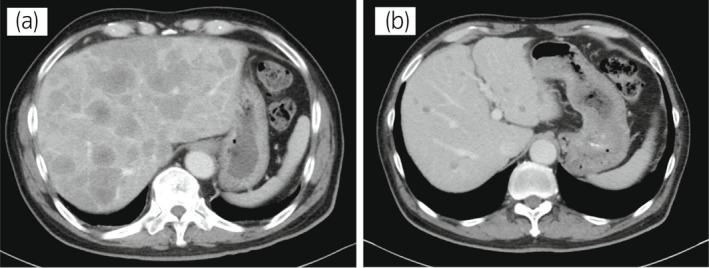

70 岁男性被诊断为转移性 PC,cT3bN1M1b,Gleason 评分(GS)为 4 + 5 = 9,前列腺特异性抗原(PSA)水平为 40.8ng/ml,3 年前伴有胸椎转移。 对前列腺进行联合雄激素阻断 (CAB) 治疗和质子放射治疗 (78.0Gy/39fr)。 PSA 水平降至 <0.01ng/ml,CAB 在 2.5 年后停止。 停止 CAB 五个月后,他出现背痛,PSA <0.01 ng/ml。 计算机断层扫描 (CT) 扫描检测到多处肝、骨和淋巴结转移,神经元特异性烯醇化酶 (NSE) 水平高达 171ng/ml(图 1a)。 骨转移活检显示神经内分泌前列腺癌 (NEPC) 的诊断(图 2),患者被转诊至佳学基因合作医院。 内分泌肿瘤精准治疗医生用顺铂、依托泊苷和亮丙瑞林治疗。 第三个疗程后,转移部位明显缩小(图 1b)。 顺铂和依托泊苷治疗 1 年,但患者因神经病变要求停药。 他开始服用恩杂鲁胺。 治疗 3 个月后,患者出现背痛和左锁骨下淋巴结肿大(图 3a)。 肝转移保持不变,顺铂治疗后缩小。 通过肿瘤精准用药850基因检测证实了 BRCA2 突变。根据基因检测结果,主治肿瘤科医生给予了奥拉帕尼。 三个月后,背痛好转,淋巴结转移缩小,确定为部分缓解(PR)(图3b)。 肝转移灶保持不变。